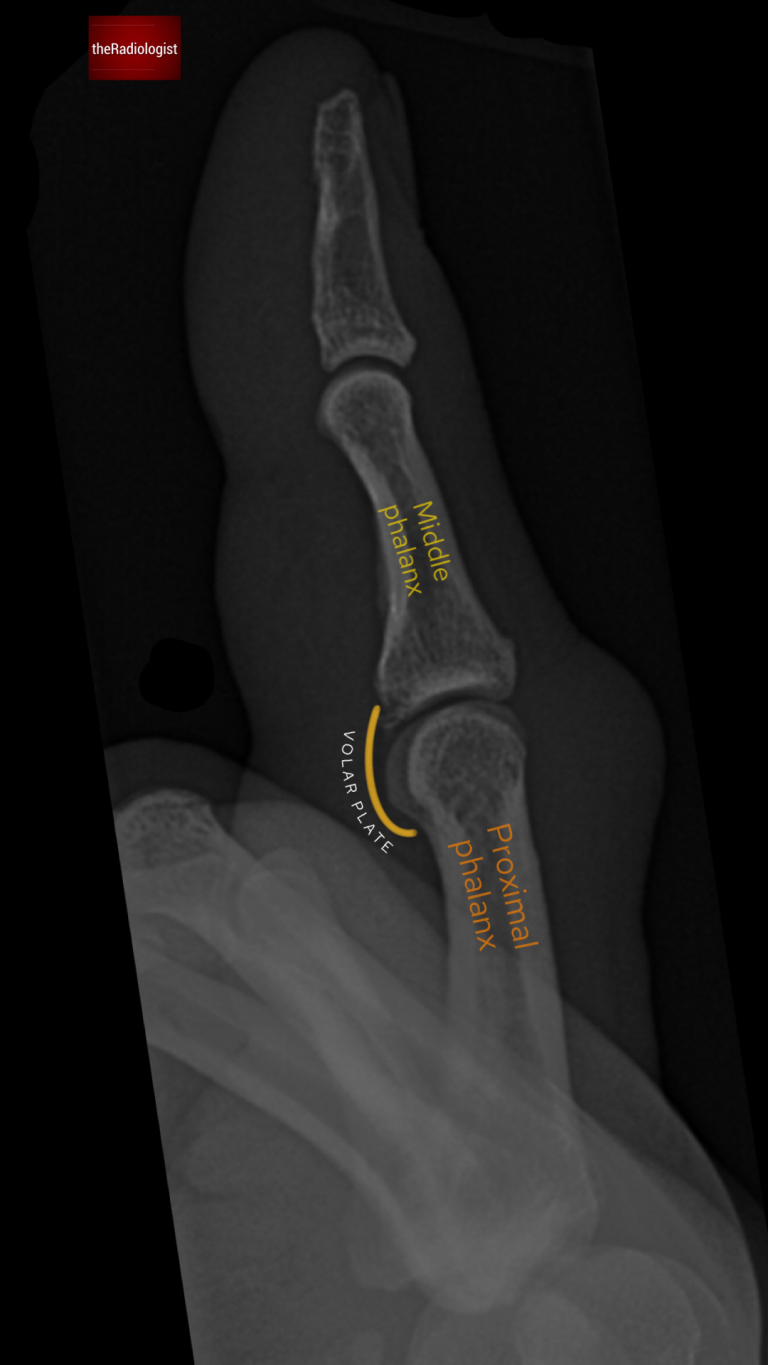

The volar plate is a fibrocartilaginous structure that stabilizes the PIP joint and prevents hyperextension.

• It originates from the proximal phalanx and inserts onto the base of the middle phalanx.

The volar plate stablises the proximal interphalangeal joint (PIPJ) and inserts onto the base of the middle phalanx.